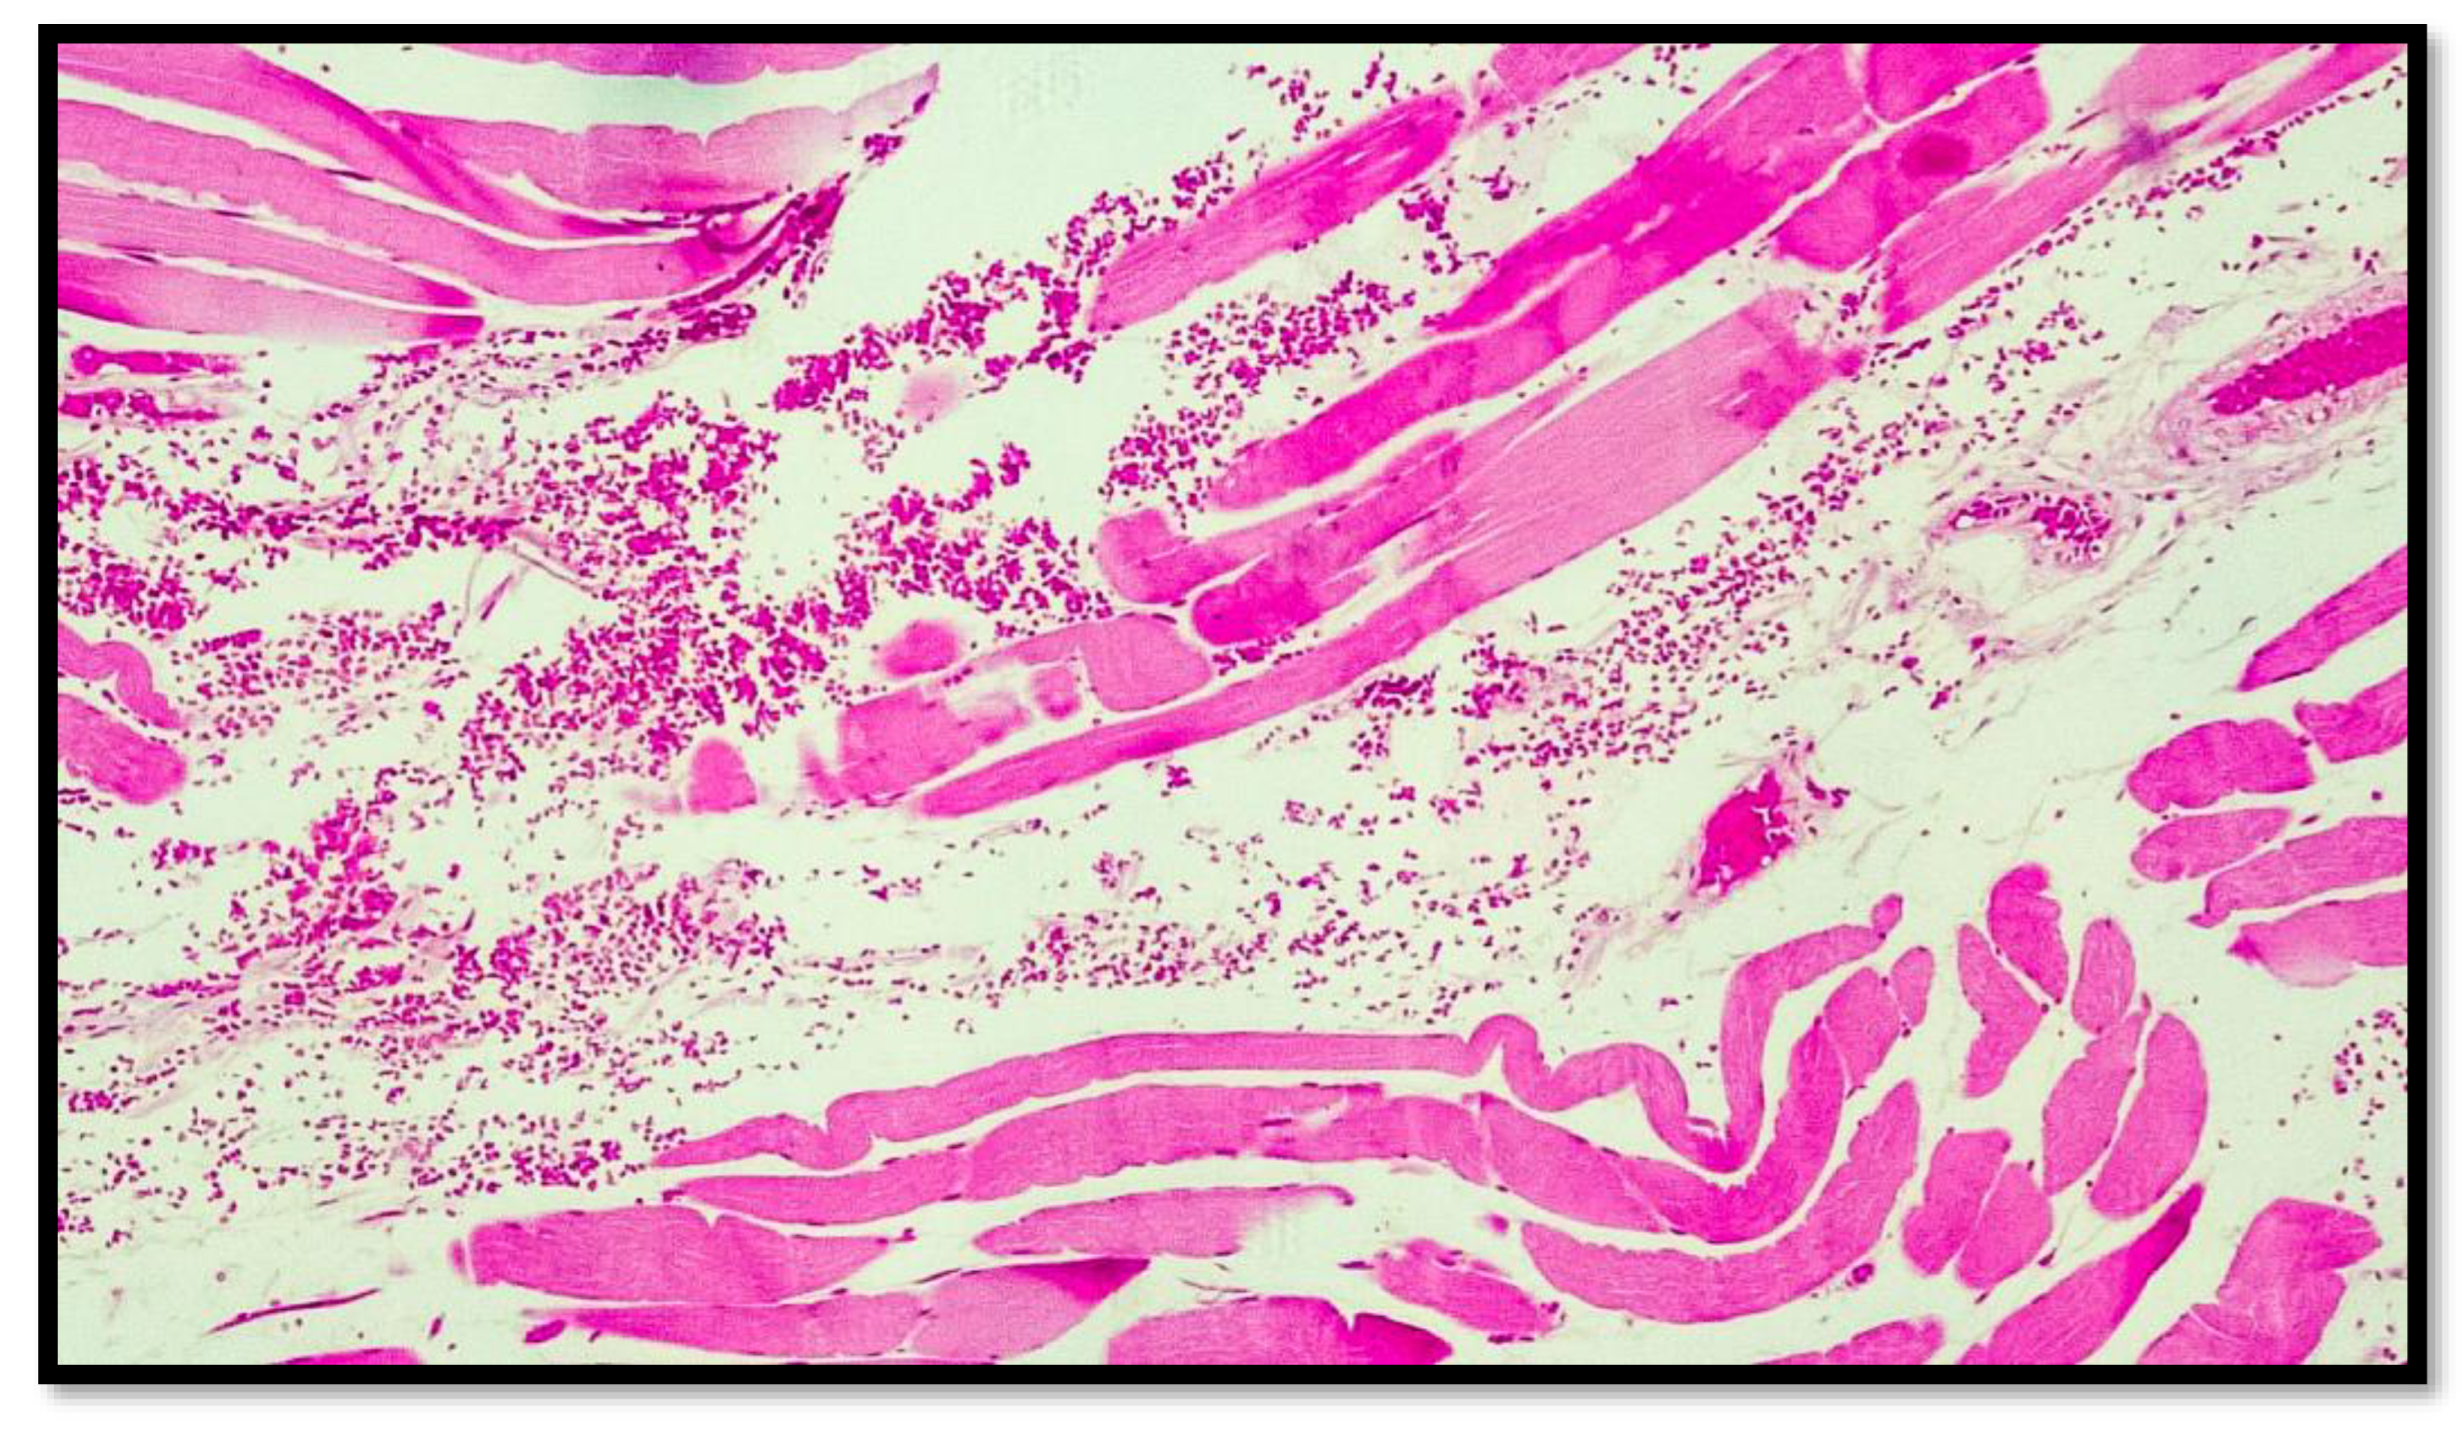

In all eight cases of death by hanging, abundant hemorrhagic infiltrate was consistently observed among the muscle fibers of the sternocleidomastoid muscles near the areas of sternal insertion (Figure 2, Figure 3, Figure 4, Figure 5 and Figure 6).

Histological preparation belonging to another subject showing the same characteristics mentioned in Figure 2. Note the presence of the blood red cells interspersed between the muscle fiber cells with the presence of segmentation of the muscle compartment (hematoxylin–eosin, Diapath S.p.A.). Original magnification, 4×.

Photomicrograph showing more detailed striated muscle fiber cells with interspersed red blood cell extravasations (black arrow) (hematoxylin–Eosin, Diapath S.p.A.). Original magnification, 10×.

Routine preparation showing, at higher magnification, the presence of extravasated red blood cells between the striated muscle fibers, and the presence of connective tissue between the muscle fibers (hematoxylin–Eosin, Diapath S.p.A.). Original magnification, 20×.